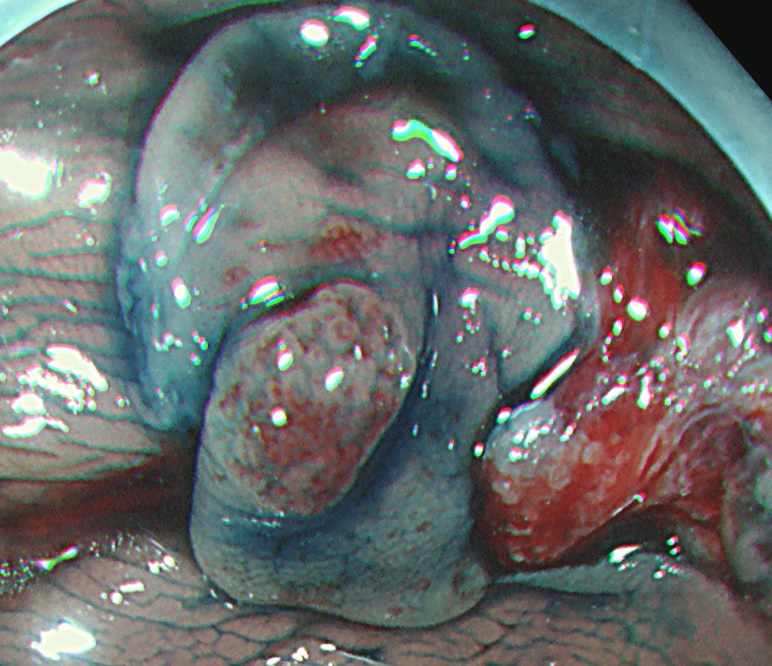

Extended Cold法法で切除された検体は「目玉焼き」のようになります。「黄身」が病変で、「白み」が周囲の正常組織(余白、マージン)です。

腫瘍の取り残しを防ぐために「白み(余白)の大きな目玉焼き」にすることが、最大のポイントです。